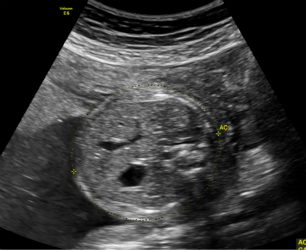

2.妊娠18周~24周超声检查:主要进行胎儿结构畸形的系统筛查。此时期胎儿各器官已发育成熟,系统产前超声检查可记录胎儿各器官结构包括头颅、面部、胸腹腔、心脏、肝脏、双肾、肢体及胎盘等结构,可发现大多数胎儿结构畸形。此阶段是观察胎儿结构和诊断胎儿畸形黄金时段,我们建议所有孕妇在此阶段务必接受一次超声检查。

只需要选择高档二维彩色系统产前超声检查,它包括胎儿结构29张图片,主要观察胎儿发育与结构是否正常。